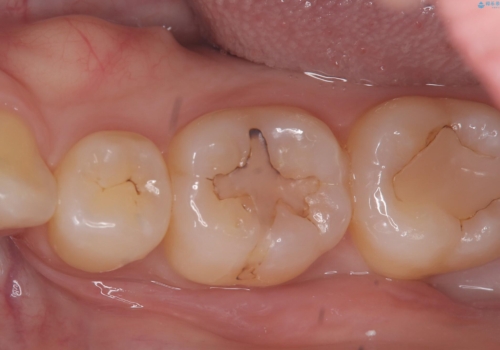

オールセラミッククラウンの膨隆で下部鼓形空隙を適切な大きさに調整しました。

物が詰まりやすく歯茎が腫れる